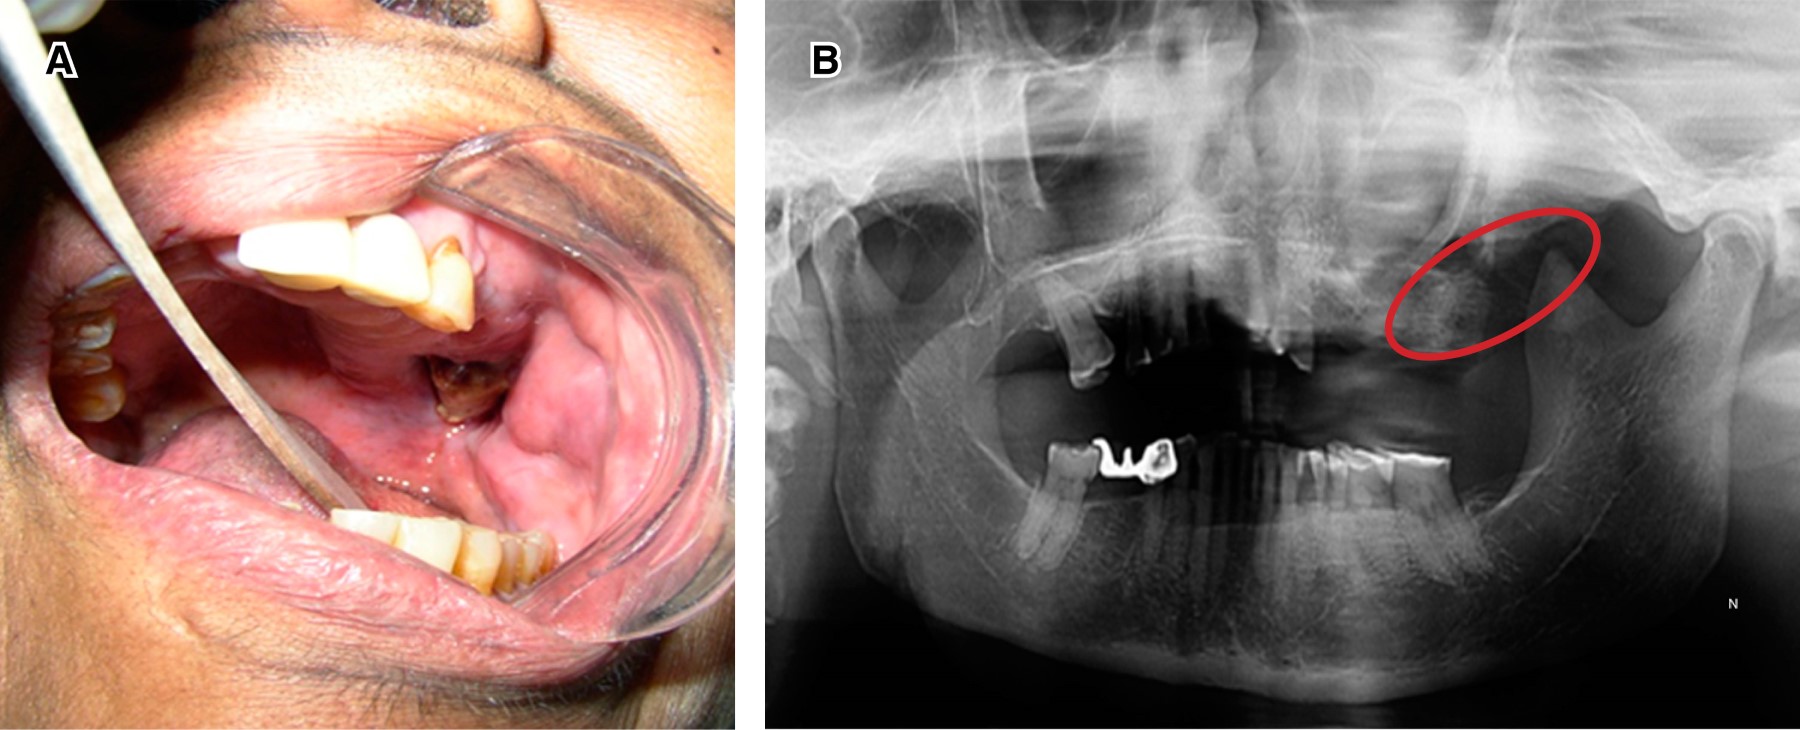

Surgery. Oncological surgery is defined as the total or partial resection of head and neck malignant neoplasm by surgical interventions. Its purpose is to eliminate cancer in a curative way, preserving as far as possible the function of the affected organs, producing acceptable aesthetic results and preventing the appearance of other tumors. The elaboration of maxillofacial prostheses is essential to restore lost functions of speech, phonation, mastication and swallowing, supporting the aesthetics of the patient to achieve a better life quality. Figure 6 shows a post-operated patient. A right-sided maxillectomy was performed due to squamous cell carcinoma, which caused an intraoral defect, a permanent obturator whose function is to separate the nasal from oral cavity was placed, so patient can feed and communicate.11-13